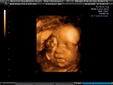

23 haftalık gebelik, hamileliğin ikinci trimesterinin sonlarına yaklaşıldığı bir dönemi ifade eder. Bu süre zarfında, hem anne hem de bebek için birçok önemli gelişim ve değişiklik yaşanmaktadır. Bu makalede, 23 haftalık gebelik dönemindeki fiziksel ve duygusal değişimlerin yanı sıra, bebeğin gelişimi, anne adayının sağlığı ve dikkat edilmesi gereken hususlar ele alınacaktır. Bebeğin Gelişimi23 haftalık gebelikte bebek, hızla büyümeye devam etmekte ve birçok önemli gelişim sürecinden geçmektedir. Bu dönemde, bebeğin gelişimiyle ilgili bazı önemli noktalar şunlardır: